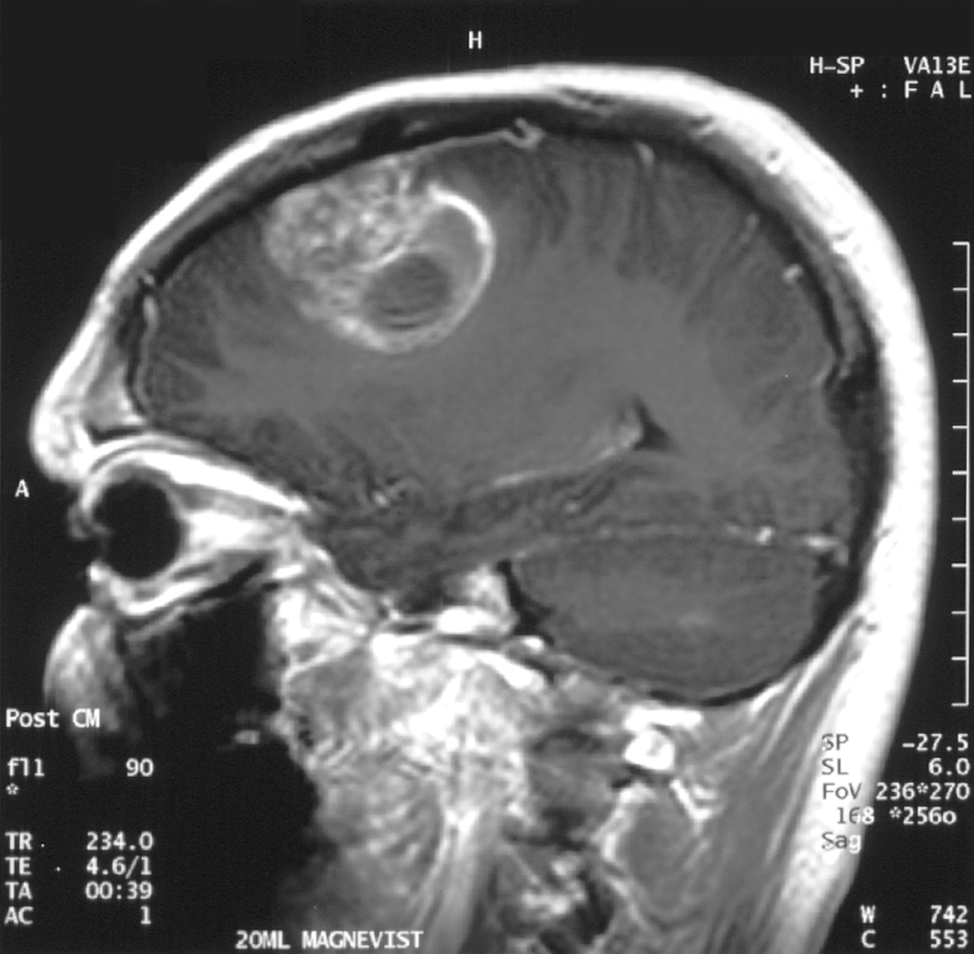

; MRI

: T1 강조 영상에서는 종양이 약간 저신호역, T2 강조 영상에서는 종양과 그 주변의 뇌부종이 고신호역이 된다. 가돌리늄을 사용한 조영 MRI에서는 종양의 변연이 고신호역이 되는 한편, 종양 내부는 괴사 등을 반영하여 저~고신호역이 뒤섞인 영상이 되는 경우가 많다. 이 소견을 링 강화라고 칭한다. 또한, 링 강화는 교모세포종에 특이적인 소견이 아니며, 뇌농양, 전이성 뇌종양 등이 감별로서 거론되는 경우가 많다.

- MRI: T1 강조 영상에서는 종양이 약간 저신호역, T2 강조 영상에서는 종양과 그 주변의 뇌부종이 고신호역이 된다. 가돌리늄을 사용한 조영 MRI에서는 종양의 변연이 고신호역이 되는 한편, 종양 내부는 괴사 등을 반영하여 저~고신호역이 뒤섞인 영상이 되는 경우가 많다. 이 소견을 링 강화라고 칭한다. 또한, 링 강화는 교모세포종에 특이적인 소견이 아니며, 뇌농양, 전이성 뇌종양 등이 감별로서 거론되는 경우가 많다.

- MRI: T1 강조 영상에서는 종양이 약간 저신호역, T2 강조 영상에서는 종양과 그 주변의 뇌부종이 고신호역이 된다. 가돌리늄을 사용한 조영 MRI에서는 종양의 변연이 고신호역이 되는 한편, 종양 내부는 괴사 등을 반영하여 저~고신호역이 뒤섞인 영상이 되는 경우가 많다. 이 소견을 링 강화라고 칭한다. 링 강화는 교모세포종에 특이적인 소견이 아니며, 뇌농양, 전이성 뇌종양 등이 감별로서 거론되는 경우가 많다.